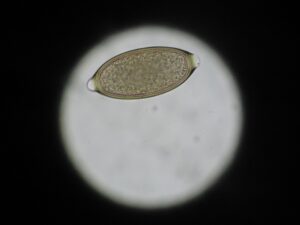

わんにゃん通信No.838「糞便検査のプロになる!」

こんにちは。   1年生の動物臨床検査学実習では、寄生虫に関する検査を行っています。 今回は、硫酸亜鉛を使った遠心浮游法で「何か」を見つけます。 方法は、飽和食塩水ではなく硫酸亜鉛を使用します。   先生に用意して頂いた糞便を溶かします。   そこまでは一緒ですが、次に試験管内に少し余裕を持たせて遠心機で回します。 その後表面張力ができるまで硫酸亜鉛を追加し3分待ちます。 さあ、何が見えたのでしょうか。   まずは、こちら。   そしてこちら。   何がいるかを見つけて、それが何かを調べてレポート提出します。 これを繰り返す事によって、糞便検査をマスターします。   ちなみにまだレポート提出前なので、ここに答えは書けませんm(_ _)m 興味のある方は調べてみてください(o^∇^o)   ↓↓クリックお願いします